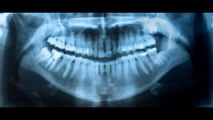

Dr. Butterman uses the CEREC Omnicam to can a Digital Impression of your teeth. Instead of filling a tray with impression “goop” that you must bite into and hold in your mouth until it hardens, the Omnicam takes seconds to take a digital impression. With the CEREC Omnicam working in conjunction with the CEREC milling unit, it leads to long-lasting, beautiful dental restorations.